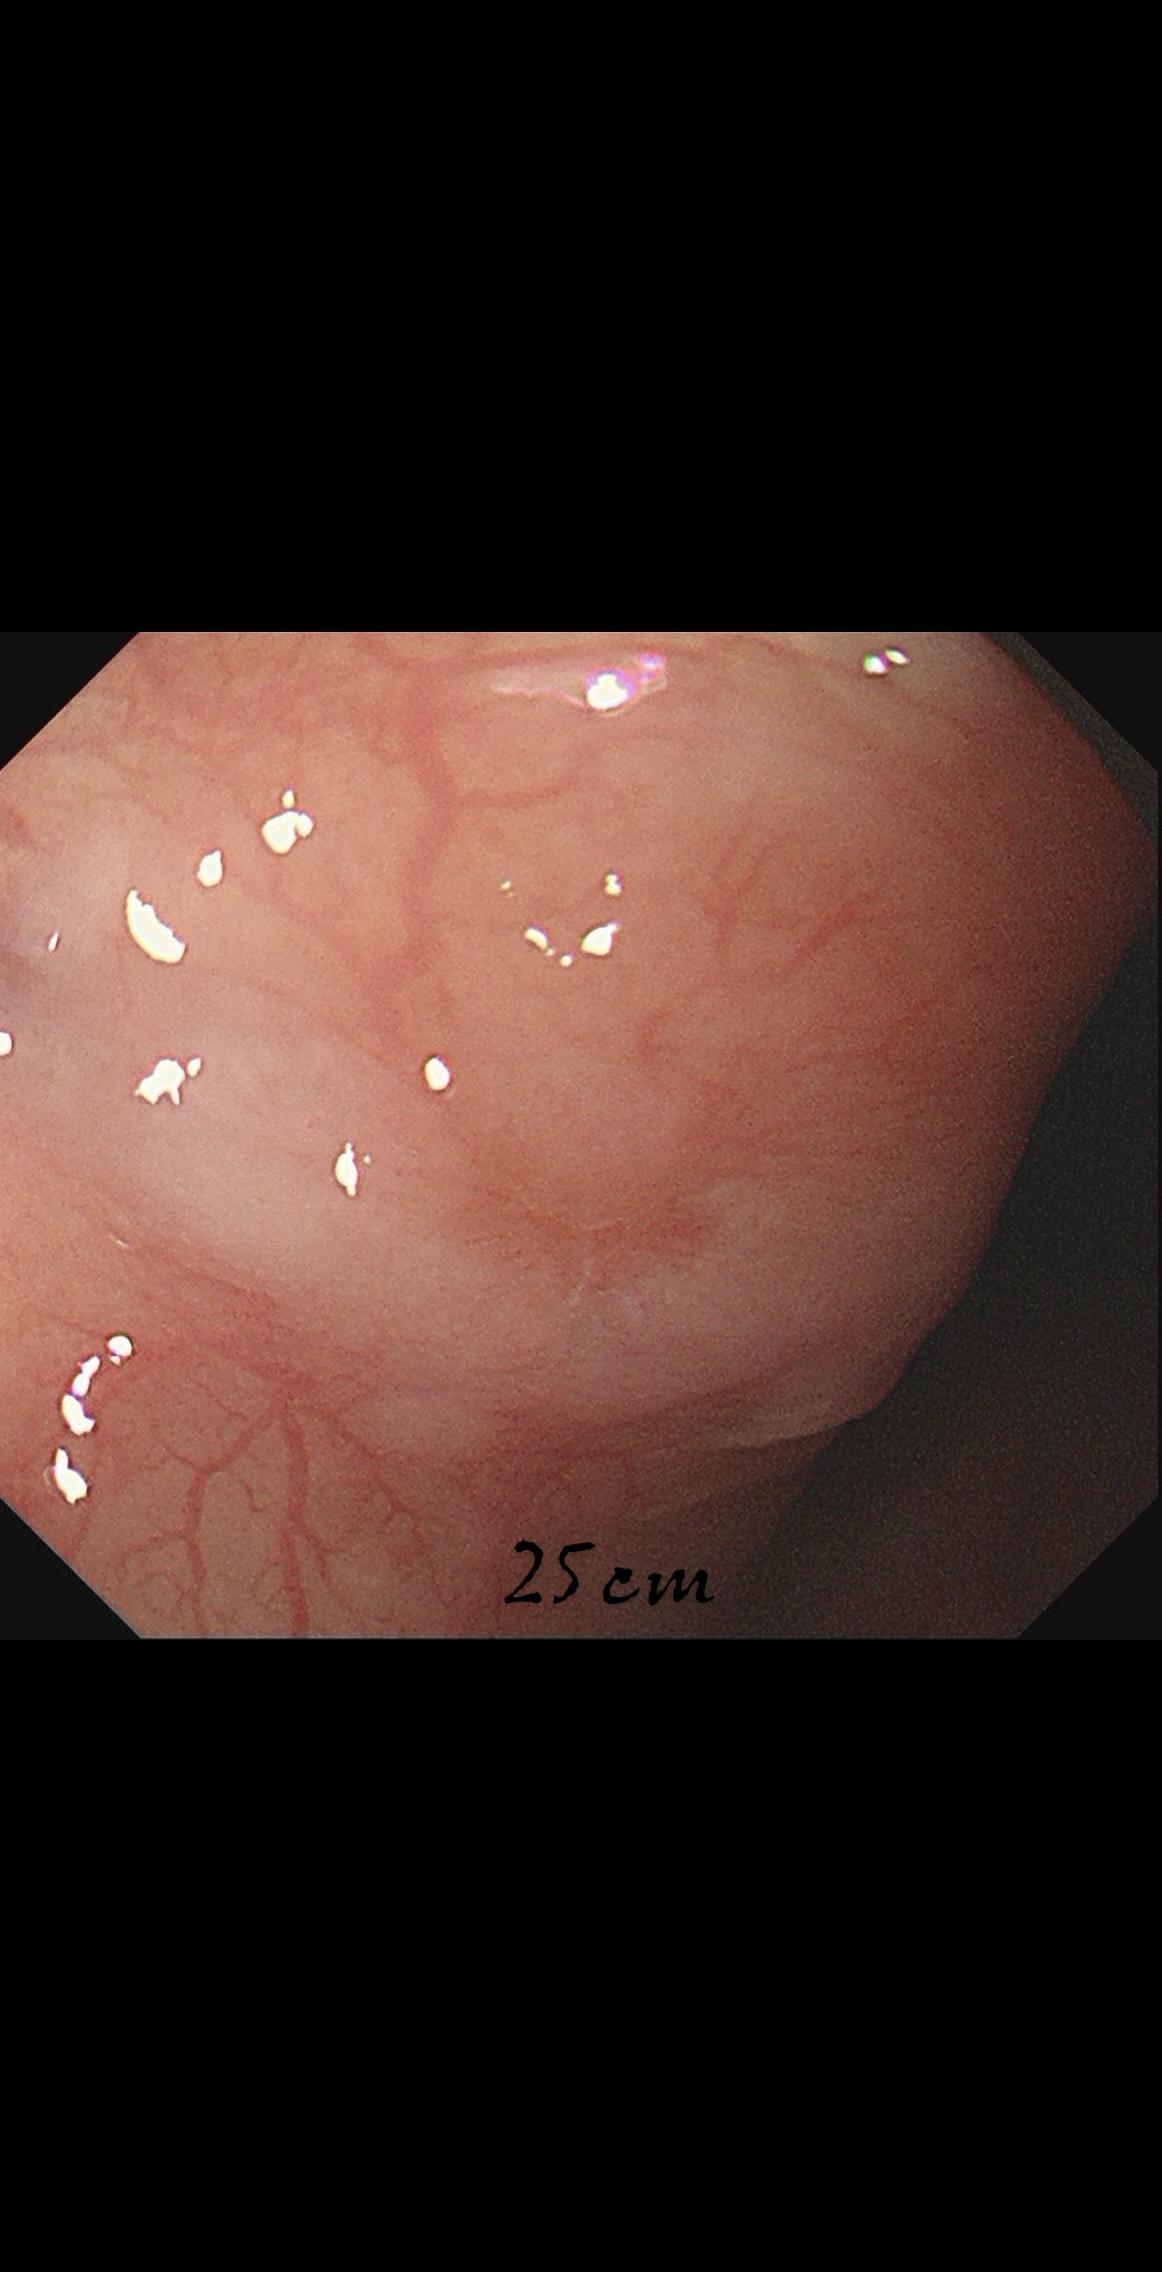

女,73岁,食管双发病变。泰州人,入院系统体检,首次胃镜检查,上段16-19cm见长条状病变,肛侧碘染局部不染;25cm处见一2mm粗糙潮红黏膜,浅凹陷,放大疑似R型不规则血管,卷发样改变,淡染,均行ESD切除。